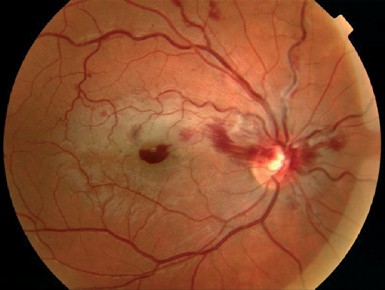

<감압망막병증(ocular decompression retinopathy)>

감압망막병증이란,

수술전 안압이 높던 환자에서 녹내장 수술이후 안압이 갑자기 떨어지면서,

안구내에서 출혈이 발생하는 경우를 의미합니다.

술전 안압이 매우 높았던 경우에서 수술후 갑자기 안압이 훅떨어지게되면,

시신경 유두부위에서 눌리고, 밀려있던 사상판이

안구내쪽으로 빨려들어오는 형태변화가 발생합니다.

이로인해서 시신경유두주위에 있던 망막 정맥이 폐쇄되면서

망막정맥폐쇄가 발생하는 현상입니다.

소아에서 더잘 발생한다고 알려져 있습니다.